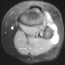

XRAY EVALUATION:

Radiographic examination of the left knee revealed no osseous abnormalities . A fullness of the soft tissues was evident over the fibular head. MRI examination of the left knee displayed a 2 cm. by 0.8 cm. lobulated mass in the region of the common peroneal nerve with no enhancement . On the T-2 weighted sequences there was abnormal increased signal of the tibialis anterior, extensor digitorum longus and peroneus longus muscle bellies suggesting atrophy . EMG/NCS were performed which clearly documented electrodiagnostic evidence of a severe peroneal neuropathy distal to the take-off of the nerve to the short head of the biceps.